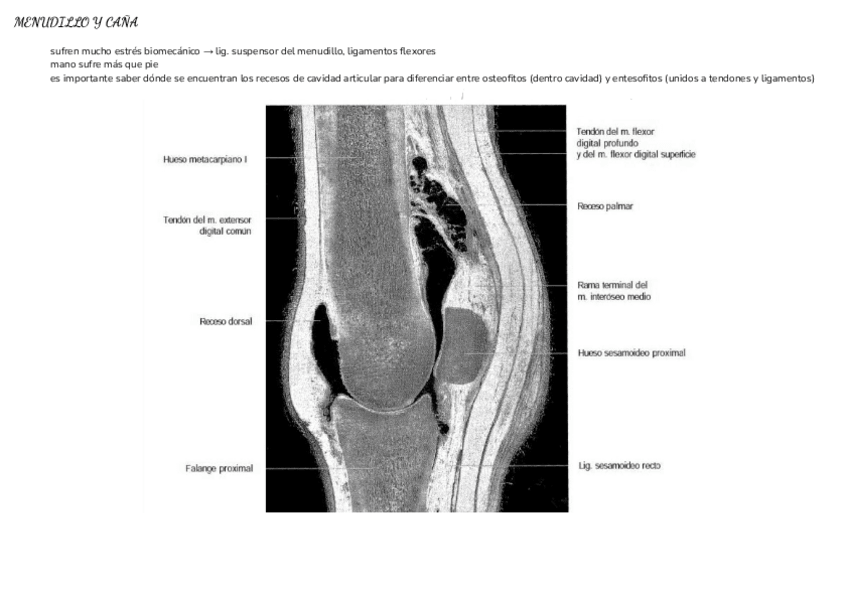

He publicado nuevos apuntes de 4º Diagnóstico Por Imagen: TEMA-MUSCULOESQUELETICO.pdf

5 páginas